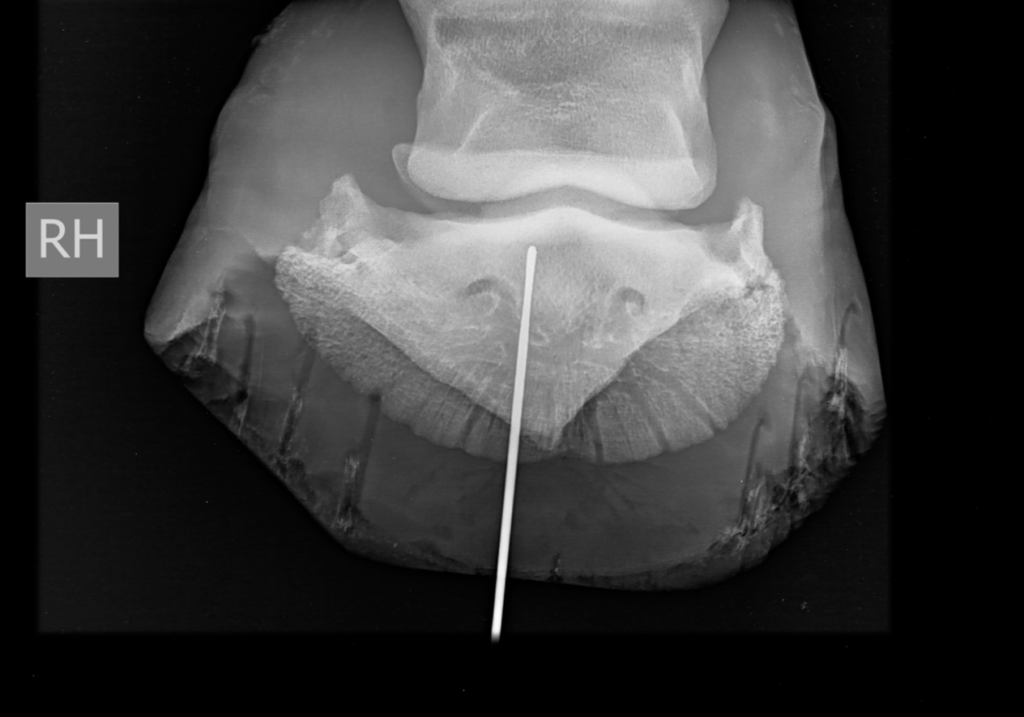

Er werden vervolgens radiografieën (LM; DPr-PlDiO) met metalen sonde genomen. Welke anatomische structuren zijn mogelijks betrokken?

DPr-PlDiO

De metalen sonde heeft een proximoplantaire richting en eindigt ter hoogte van het plantaroproximaal aspect van het hoefbeen en distaal van de distale rand van het straalbeen.

Anatomische structuren welke hoogstwaarschijnlijk betrokken zijn bij deze nageltred zijn: de diepe buigpees, lig. sesamoideum distale impar, de bursa podotrochlearis en de plantarodistale recessus van het hoefgewricht.

Geen bot afwijkingen vastgesteld.